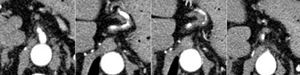

As the abdominal pain continued to persist, even with high doses of opioids, a computed tomography (CT) angiography study was performed. The CT showed diffuse wall thickening of the left gastric artery with an area of multi-segmental stenosis, with no abnormalities in renal and coeliac arteries (Fig. 1).

Magnetic resonance imaging (MRI) of the brain detected leptomeningeal meningovascular involvement compatible with neurosyphilis. Although the skin and laboratory findings pointed to secondary syphilis, the typical characteristics of tertiary syphilis with neurological and vascular involvement predominated and aggravated the condition. The patient was started on treatment with intravenous sodium penicillin for 14 days, with which the skin lesions cleared up and the abdominal pain gradually decreased and went away. Repeat CT-angiogram of the abdomen and pelvis showed regression of the vascular involvement.